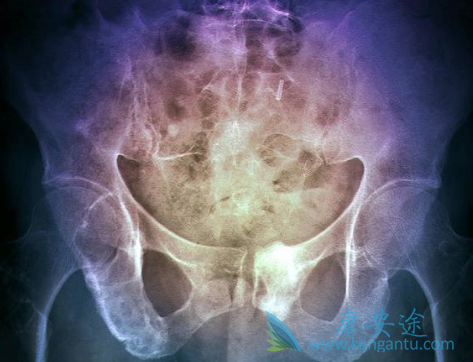

由MGUS转成骨髓瘤的危险性是非常低的:大约仅1%。而且,骨髓瘤细胞达到骨髓细胞的10-30%,生长速度还是很慢的,这个阶段称为惰性/冒烟型或无症状骨髓瘤。MGUS和这种惰性骨髓瘤数年内都发展非常缓慢,均无须积极治疗,但目前对于此类患者多是提倡早期就开始预防性的防护措施。而到最后发展就是多发骨髓瘤了,是必要积极高强度治疗的。通过以上三点这么描述,可以自然的看出病情严重程度“阶梯”,第三点也明确指出了CRAB属于器官损害,但并非是一种器官损害的代称,则需要分开来理解。C——血钙升高(>10mg/L),R——肾功能异常(肌酐>2mg/dL),A——贫血(血红蛋白〈10g/dL),B——骨骼疾病(溶骨性病变或骨质疏松症),对此,需要在临床上根据实际性的病情情况开始制定治疗方案,缓解器官损害,降低病情恶化进展的“脚步”。